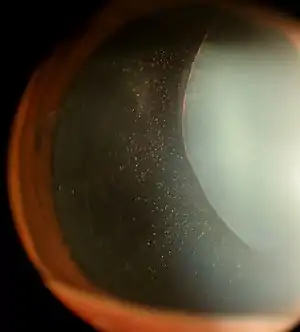

Anterior lens luxation with cataract formation in a cat

With anterior lens luxation, the lens pushes into the iris or actually enters the anterior chamber of the eye. This can cause glaucoma, uveitis, or damage to the cornea. Uveitis (inflammation of the eye) causes the pupil to constrict (miosis) and trap the lens in the anterior chamber, leading to an obstruction of outflow of aqueous humour and subsequent increase in ocular pressure (glaucoma).[1] Better prognosis is valued in lens replacement surgery (retained vision and normal intraocular pressure) when it is performed before the onset of secondary glaucoma.[2] Glaucoma secondary to anterior lens luxation is less common in cats than dogs due to their naturally deeper anterior chamber and the liquification of the vitreous humour secondary to chronic inflammation.[3] Anterior lens luxation is considered to be an ophthalmological emergency.